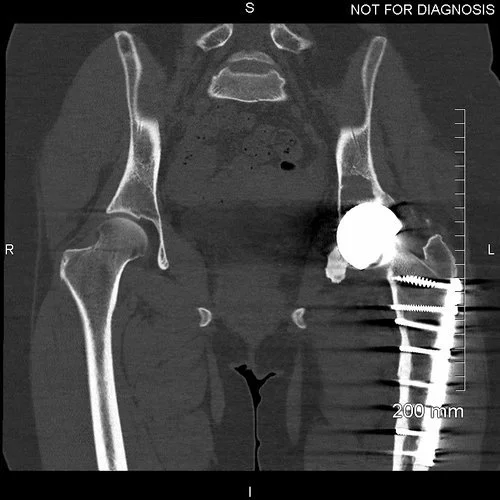

Coronal CT - This is used by the surgeon and the biomedical engineer to design the custom implant specifically to the patient’s acetabular bone stock. This CT demonstrates significant loss of bone stock relating to the left hip resurfacing.

3D CT reconstruction showing the hemipelvic defect.